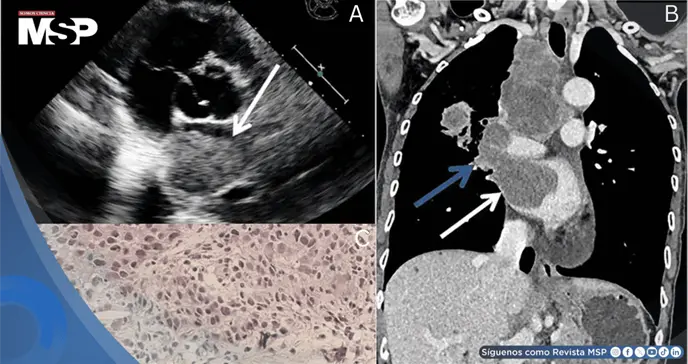

La ecocardiografía transtorácica identificó una masa hipoecoica de 5.1 × 3.4 cm en la aurícula izquierda, íntimamente relacionada con la vena pulmonar derecha.

Este hallazgo se confirmó mediante tomografía computarizada contrastada de cuello, tórax y abdomen superior, que demostró continuidad de la masa con la vena pulmonar superior derecha. Adicionalmente, se detectó un nódulo metastásico en la glándula suprarrenal derecha.

El examen microscópico mostró células neoplásicas dispuestas en nidos con patrón de crecimiento infiltrativo, marcada atipia celular y proliferación del estroma fibroso. El panel inmunohistoquímico confirmó el diagnóstico de carcinoma de pulmón de células no pequeñas, con positividad para citoqueratina, citoqueratina 7 y TTF1, expresión de PD-L1 del 22% (TPS), e índice de proliferación Ki-67 del 20%. Las tinciones para NapsinA, P40, P63 y CK5/6 resultaron negativas.